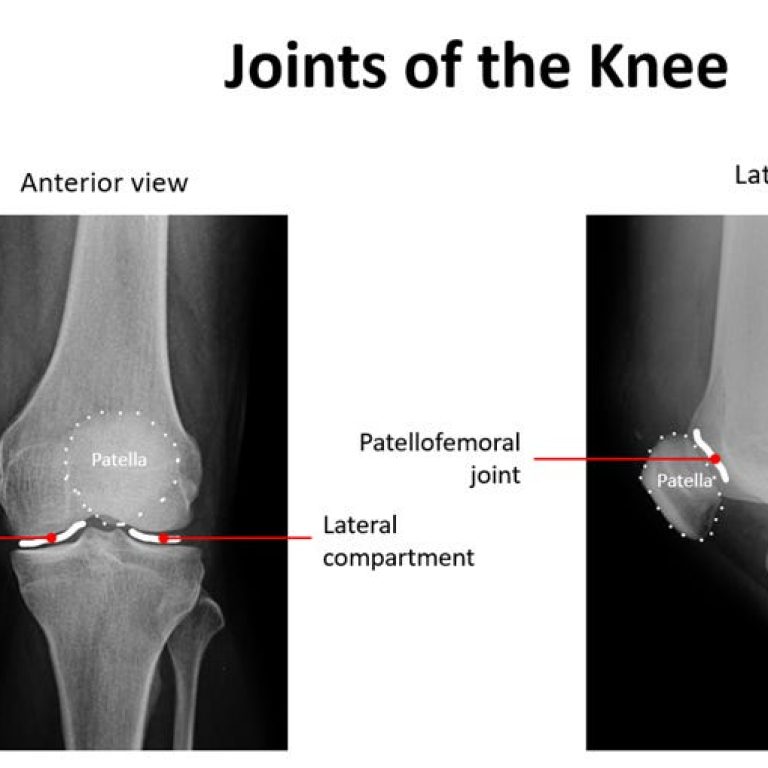

Knee osteoarthritis is a common cause of pain, stiffness, and reduced mobility, especially with age. Symptoms often develop …